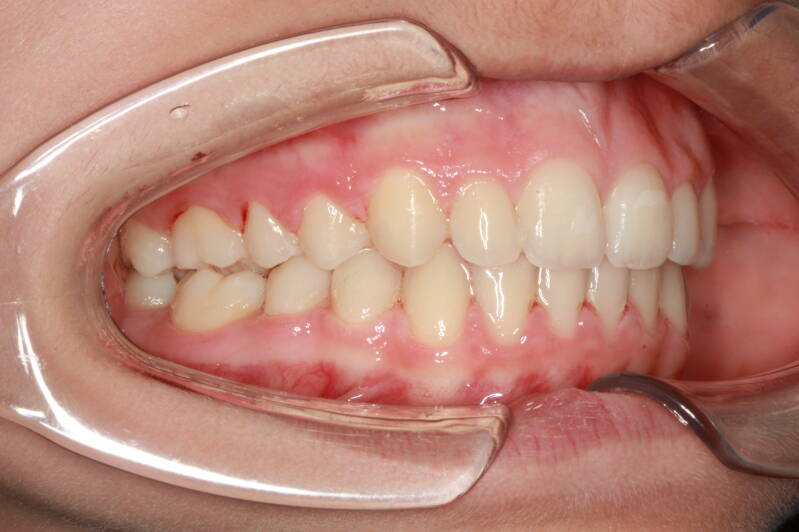

Questo mese vi presentiamo G.G. f. di15aa. Ha una seconda classe suddivisione destra molare e canina. richiesta Allineamento.

FOTO INIZIALI PRE TRATTAMENTO ORTODONTICO